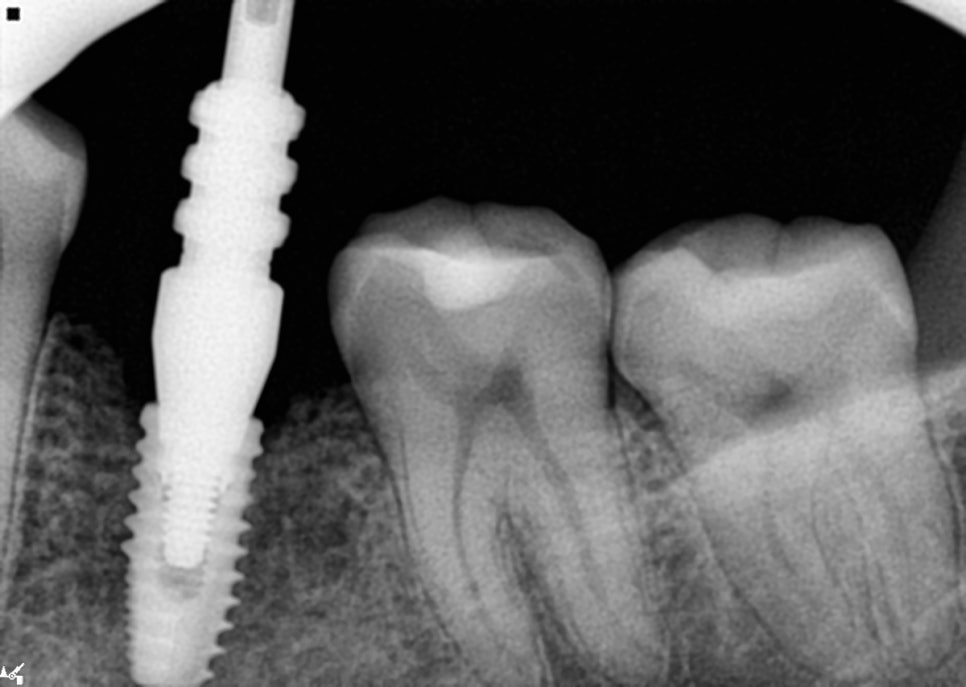

위쪽 3개 어버트먼트 장착 완료

어버트먼트는 장착 후에는 반드시

방사선 사진으로 체결 상태를

더블체크 해야합니다.

눈으로 잘 된것처럼 보이지만

그렇지 않을 수 있기때문에

꼼꼼하게 확인을 해야하기 때문이죠.